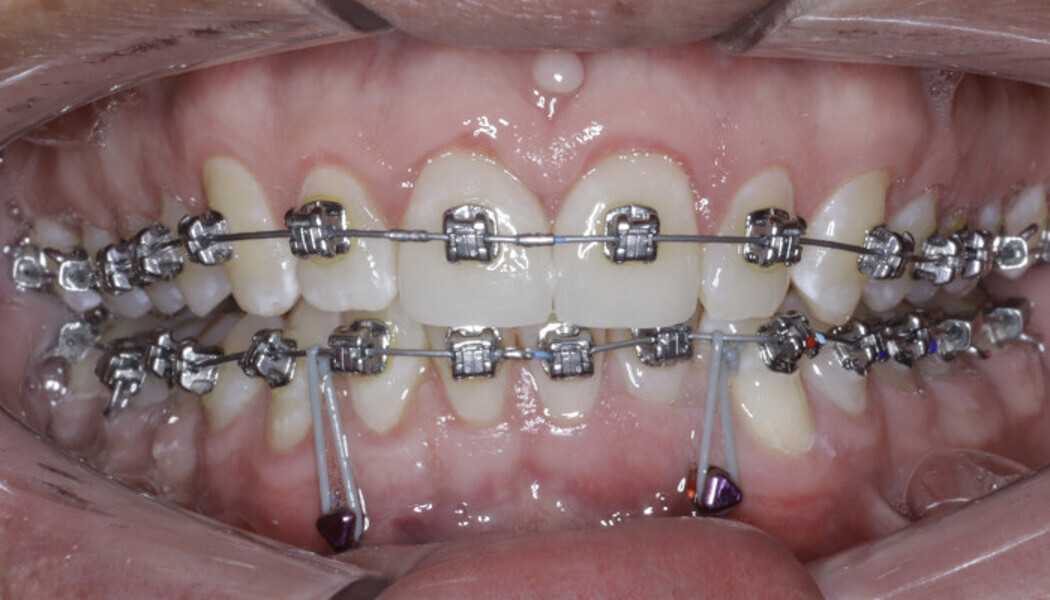

New Age orthodontics and orthopaedics with temporary anchorage devices